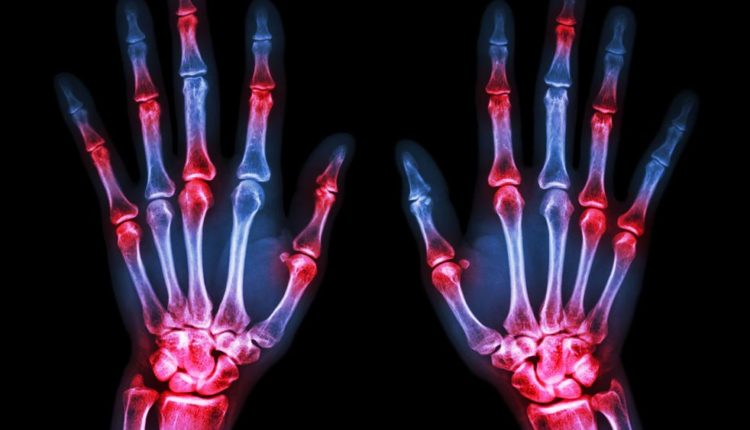

Σημαντική έγκριση νέας θεραπείας για τους ασθενείς με ρευματοειδή αρθρίτιδα

Η έγκριση του upadacitinib από την Ευρωπαϊκή Επιτροπή για ασθενείς με μέτρια έως σοβαρή ρευματοειδή αρθρίτιδα είναι ένα από τα τελευταία “καλά νέα” της χρονιάς για ασθενείς με τη συγκεκριμένη νόσο. “Σχεδόν 3 εκατομμύρια άνθρωποι στην Ευρώπη ζουν με ρευματοειδή αρθρίτιδα, η πλειονότητα των οποίων δεν επιτυγχάνει ύφεση και ενδέχεται να υποφέρει από πόνο, κόπωση, πρωινή δυσκαμψία στις αρθρώσεις και εξάρσεις”, δήλωσε ο Καθηγητής Ronald van Vollenhoven, M.D., Ph.D., Κέντρο Ρευματολογίας και Ανοσολογίας του Άμστερνταμ στις Κάτω Χώρες. “Όπως διαπιστώνεται στο μεγάλο αυτό πρόγραμμα κλινικών μελετών Φάσης 3 στη ρευματοειδή αρθρίτιδα, το upadacitinib έχει τη δυνατότητα να βελτιώσει σημαντικά τα σημεία και τα συμπτώματα της νόσου και να βοηθήσει περισσότερους ασθενείς να πετύχουν ύφεση ή χαμηλή ενεργότητα της νόσου”.